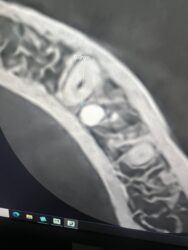

What are your thoughts on what this radiolucent area in the anterior mandible could be? Should I be concerened with placing an implant into it?

I’m not sure just from those slices but more reward and less risk in other locations. Around the mandibular midline you have your superior and/or inferior foramina relative to the genial tubercle/mental spine which can very in size greatly from pt. to pt. and often times very apical where no teeth have been before you can have more variability…

100% in agreement with @restoredsmiles While the anterior mandible is easy pickings for implants, it is very important to pay attention to things like this in the x rays.

It looks like if you drill into that spot you may get a bleeder that might be difficult to manage. I would also recommend opting for modifying your plan to stay away from that finding.